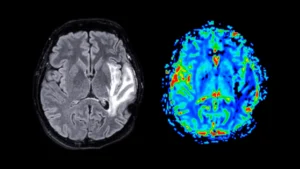

A significant advancement in medical diagnostics promises to fundamentally alter how a range of debilitating gastrointestinal disorders,...